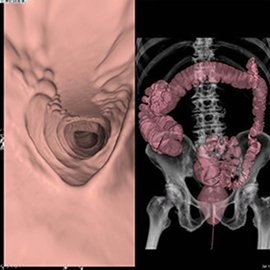

CTの検査画像例

また、CTの更新に伴い3次元画像解析ワークステーションsynapseVINCENTを最新版にバージョンアップしました。 FUJIFILM独自のAI技術を搭載し、自動抽出機能が充実したことで、整形領域をはじめ、冠動脈解析、肝切除術前シミュレーション、大腸癌術前CTcolonographyにおいて、より短時間で高精度な3D解析ができるようになりました。

閉塞性動脈硬化症(ASO)に対する下肢CTangio、肺梗塞・深部静脈血栓症の精査、外傷全身CT、狭心症疑いに対する心臓CT、外科術前精査など各科からの依頼に迅速に対応しております。